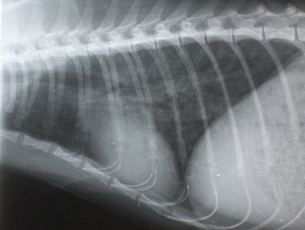

X線検査

気管支パターンが認められます。また横隔膜が斜めになり、暗い肺野の部分が多くなります。時に右の中葉や左の後葉に硬化像が認められます。

イメージ イメージ

Figure 2. 治療前のX線写真、肺のX線の透過性の亢進と気管支の肥厚を認める Figure 3. 治療3日後のX線写真、肺の透過性が低下(改善している)している。